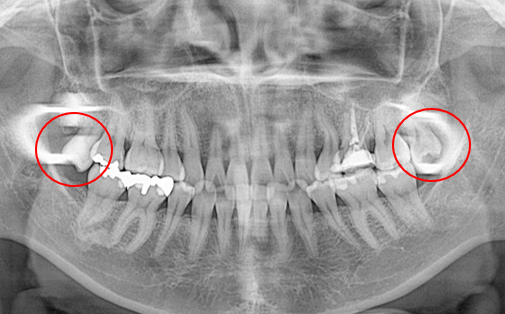

抜歯した親知らずを移植(3)

Before

After

左上の歯が折れています。折れた歯を抜き、親知らずの歯を移植しました。